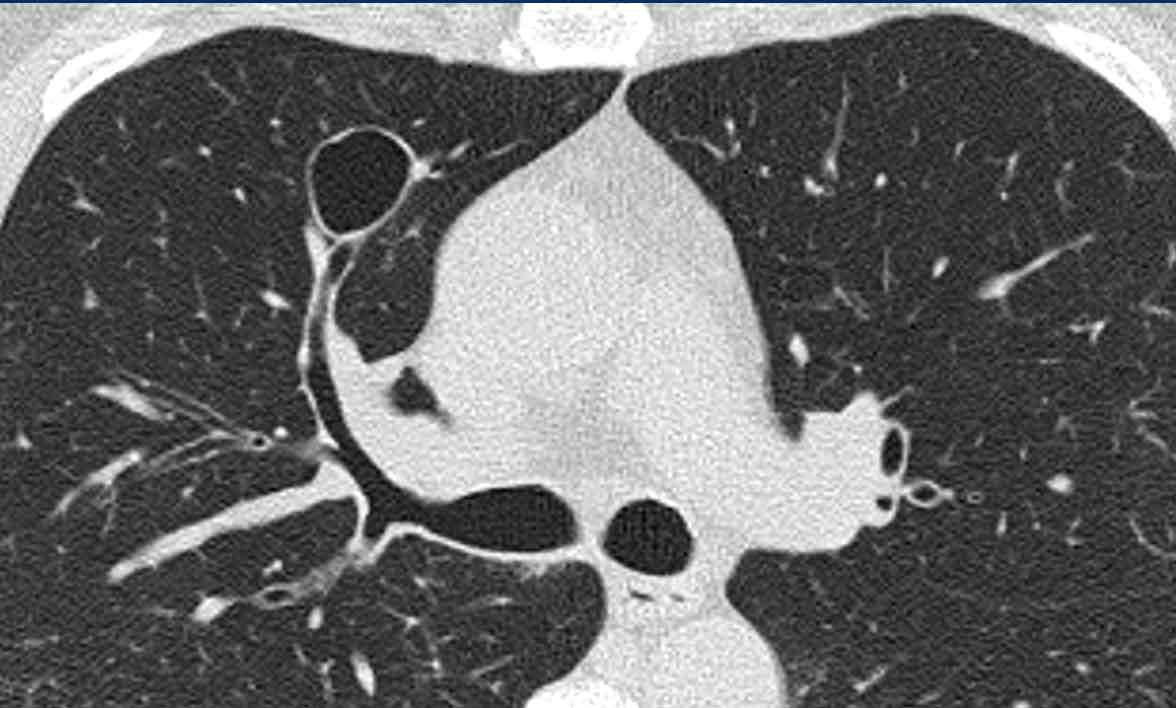

Đây là hình ảnh của một bệnh nhân nam 66 tuổi, có tiền sử hút thuốc lá và đến khám vì triệu chứng khó thở.

Nhận xét hình ảnh

Ghi nhận nhiều nang.

Một số có hình dạng bất thường và một số có dấu hiệu “cheerio” (hình vòng tròn) do hiện tượng tạo hang bên trong nốt (mũi tên trắng).

Ngoài ra còn ghi nhận một số nốt (mũi tên đen).

Bình luận

Sự kết hợp của các dấu hiệu này trên một bệnh nhân hút thuốc lá là điển hình cho chẩn đoán LCH.

Trên tái tạo mặt phẳng coronal, có thể thấy rõ ràng rằng các nang chủ yếu tập trung ở thùy trên và thùy giữa, trong khi vùng đáy phổi được bảo tồn.

Đặc biệt khi LCH còn ở giai đoạn nốt, sự phân bố này có thể là dấu hiệu hữu ích trong việc phân biệt với di căn phổi, vốn có xu hướng ưu thế ở thùy dưới.